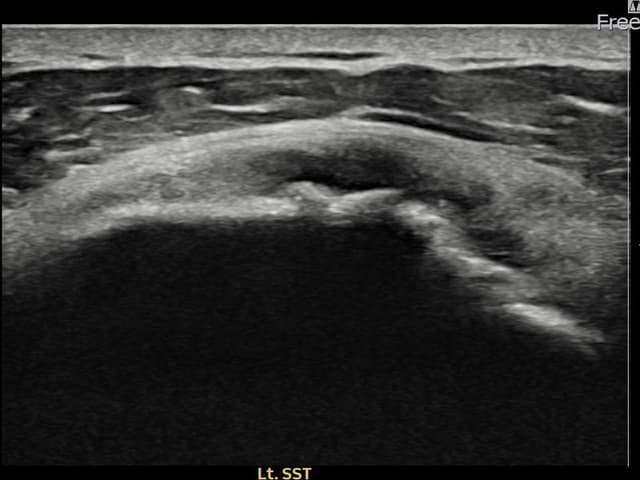

左侧 冈上肌腱 石灰化肌腱炎

9mm × 7mm